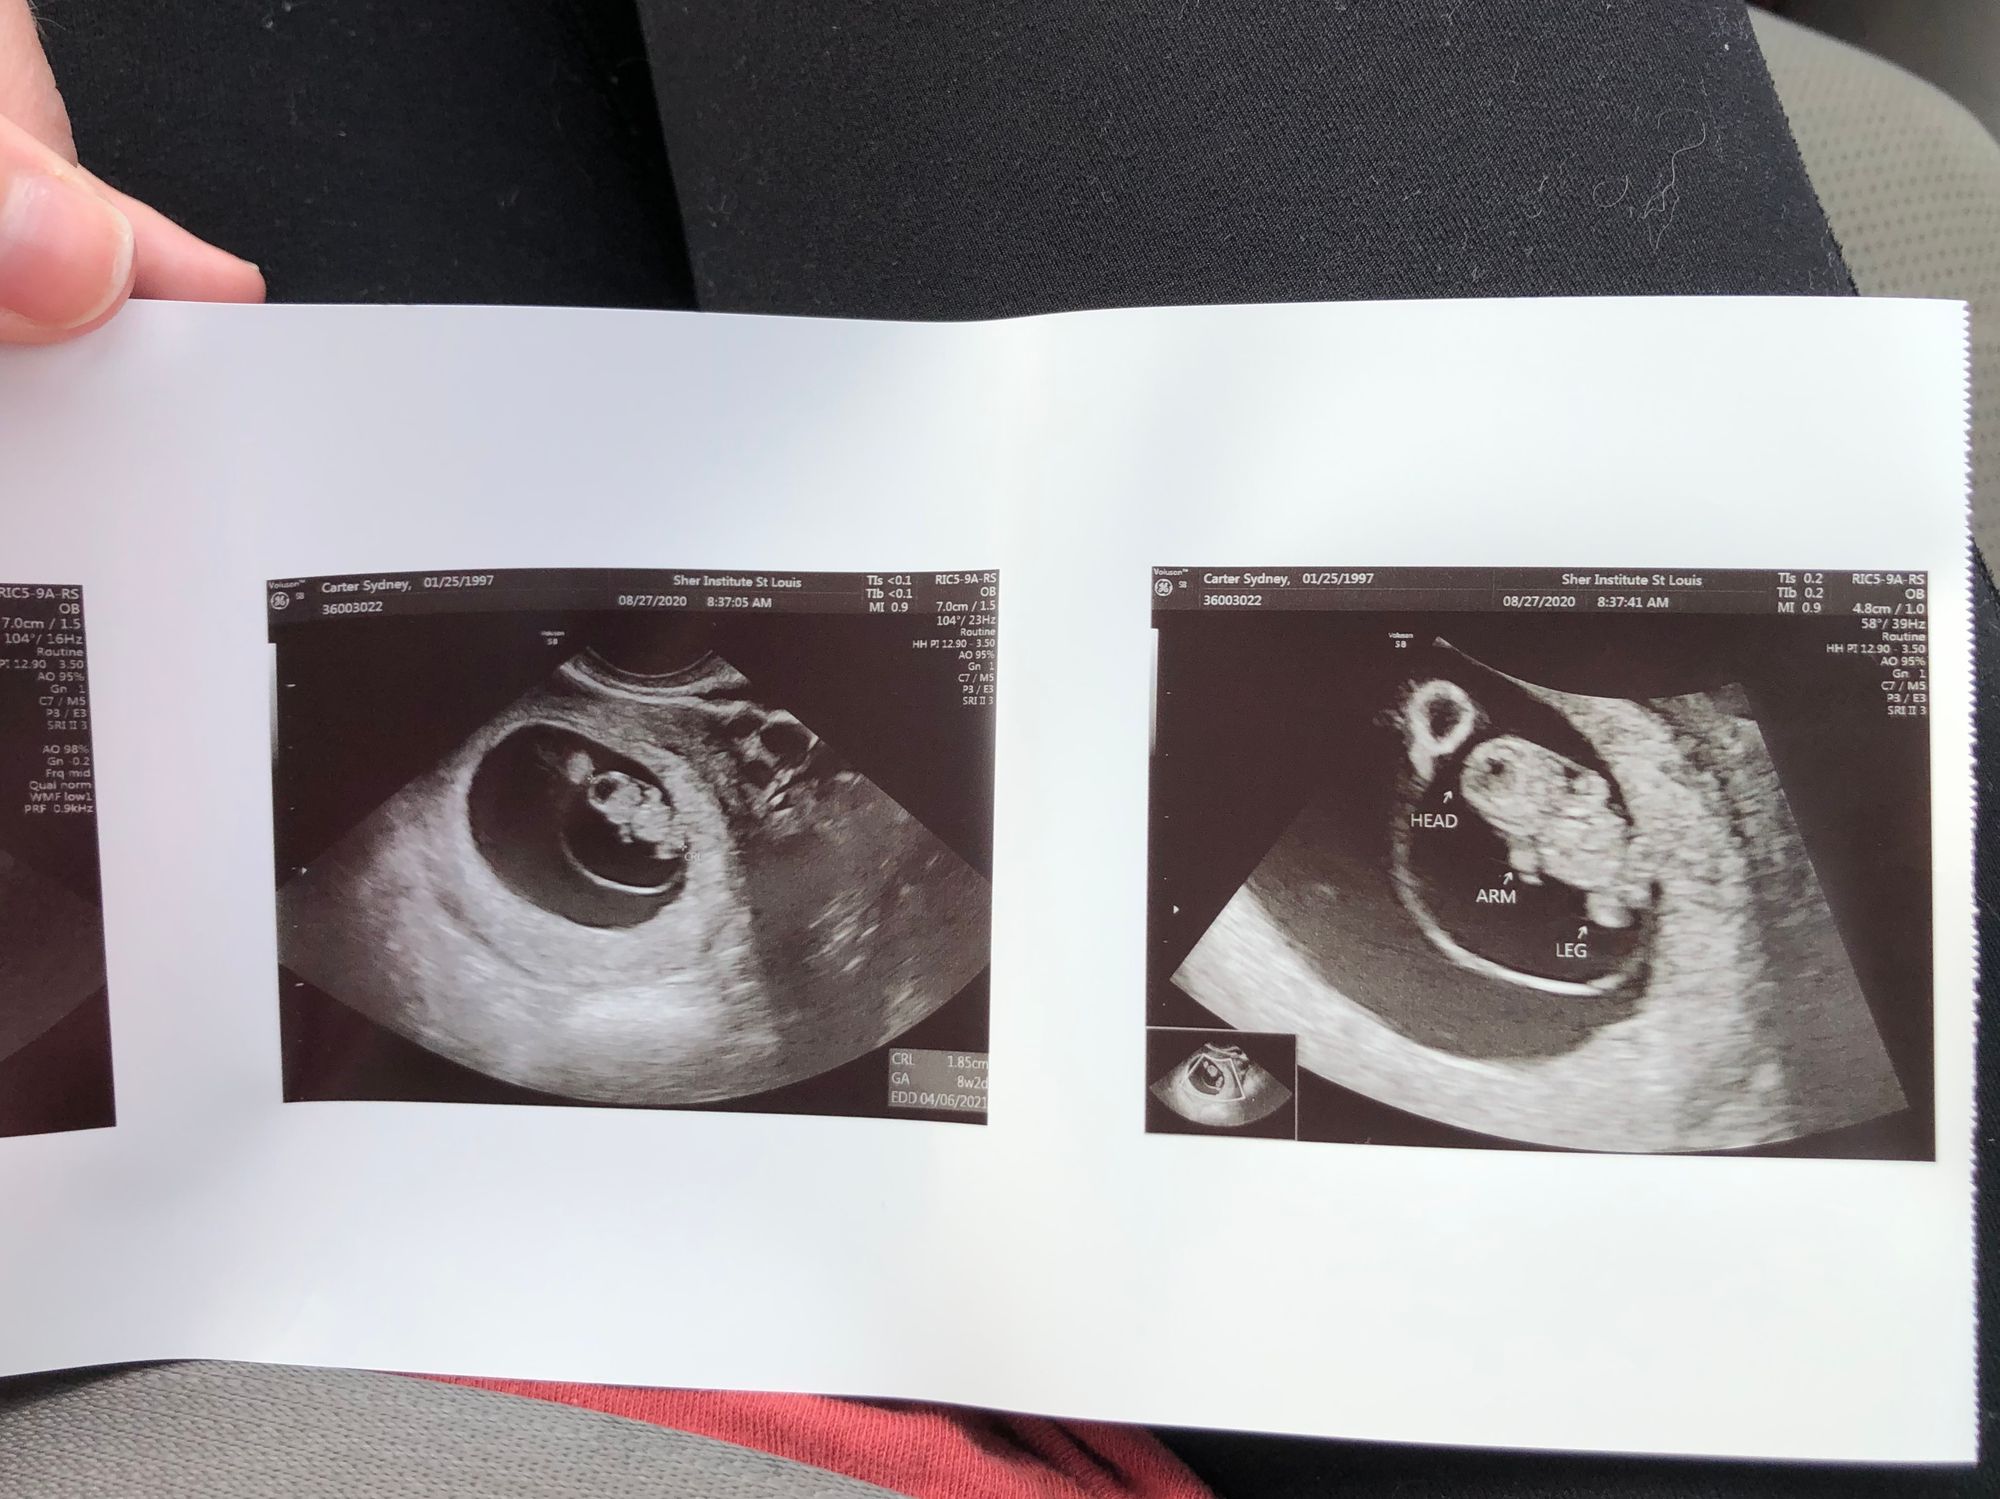

August 27: Third appointment!! 8 weeks

I was praying this one would be good too. Logan had the morning off so he was able to drive me to the appointment and wait in the car. We stopped by and grabbed some McDonald's on our way there. My stomach was going CRAZY. I met with the other Fertility Doc and she was super nice! There had been so much change within the last week! A super strong heart beat at 175 and little arms and legs are growing strong. What a relief. I'm now headed back over to Dr. Phillips office on September 8th!